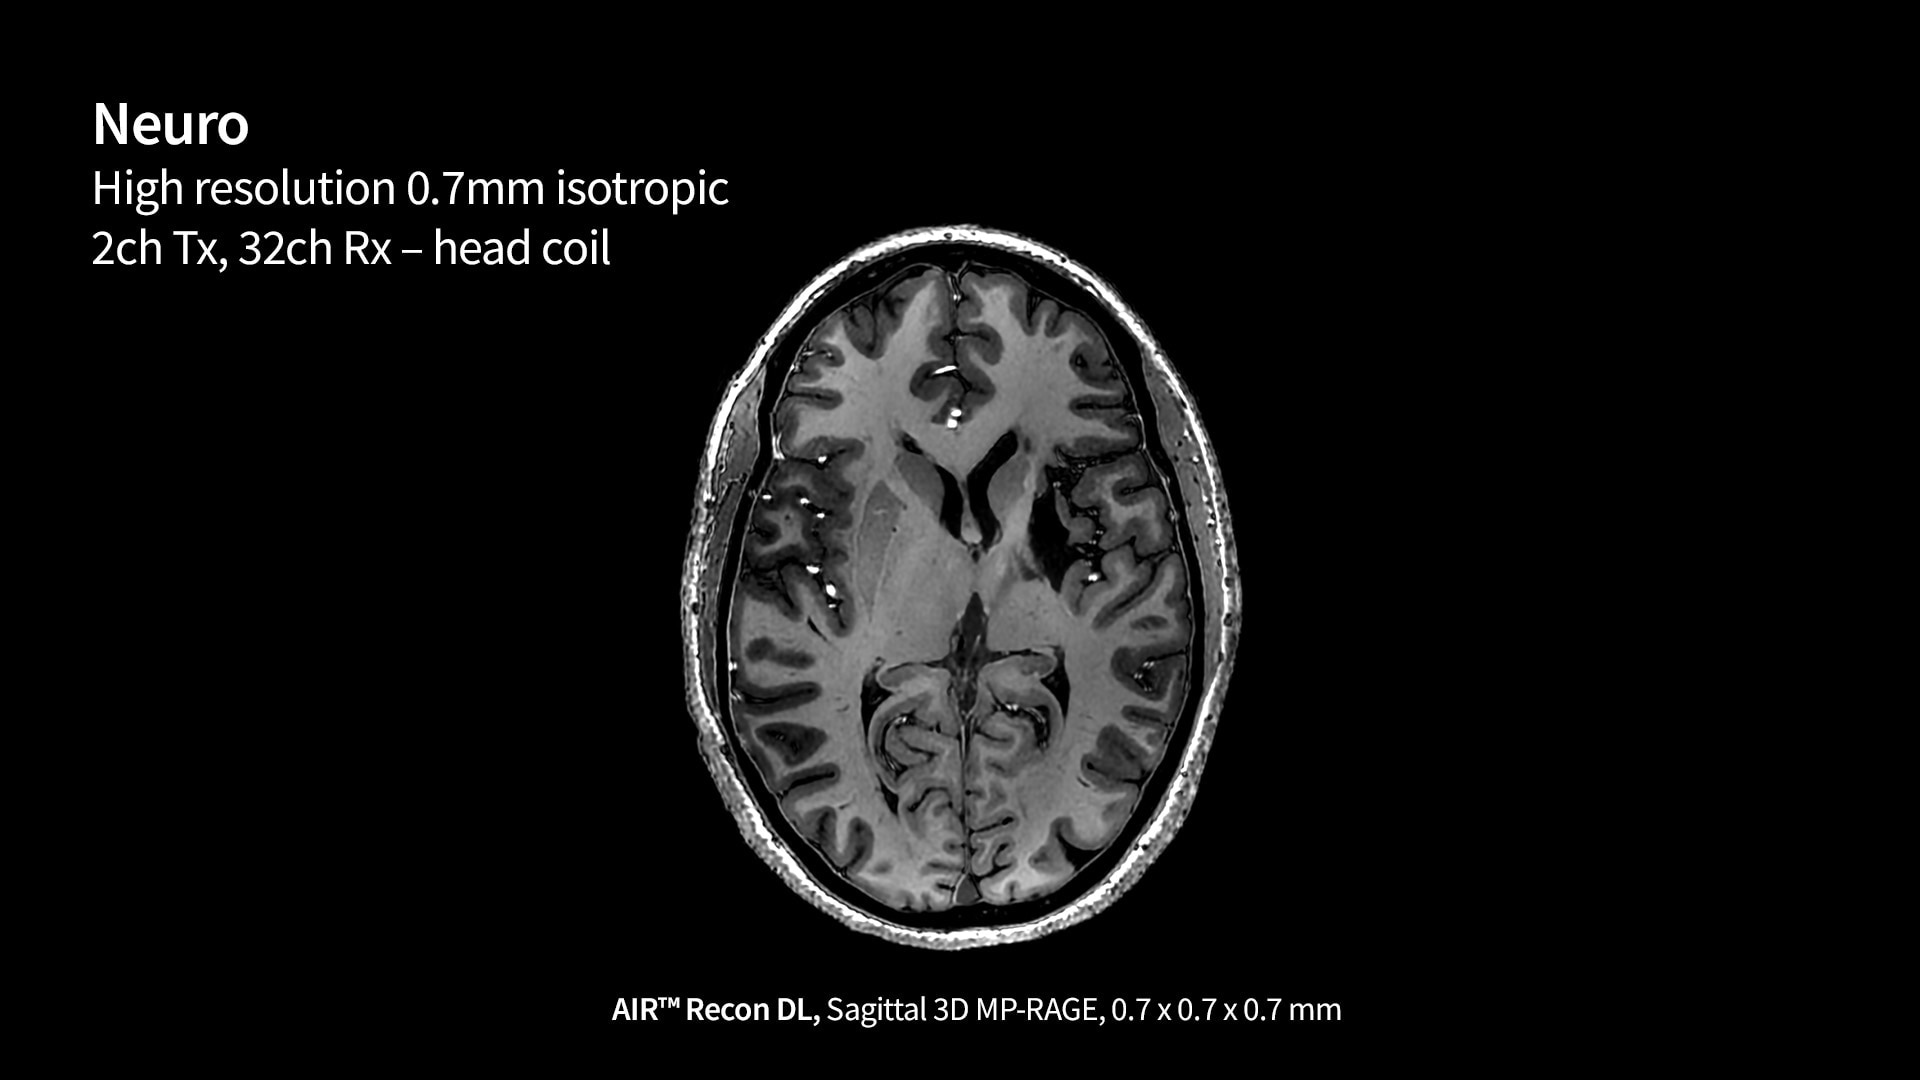

SIGNA 7T powered by a common suite of SIGNA Imaging Applications

Users have access to our latest state-of-the-art applications along with deep-learning tools like AIR x™ Brain and Knee as well as AIR™ Recon DL, while delivering the diagnostic confidence of an ultra-high-field system.

Our 7T MRI scanner is GE HealthCare’s most powerful whole-body gradient system yet. With peak amplitude of 113 mT/m and a peak slew rate of 260 T/m/s, this scanner can properly leverage the clinical capabilities and research demands that users expect from a 7T.